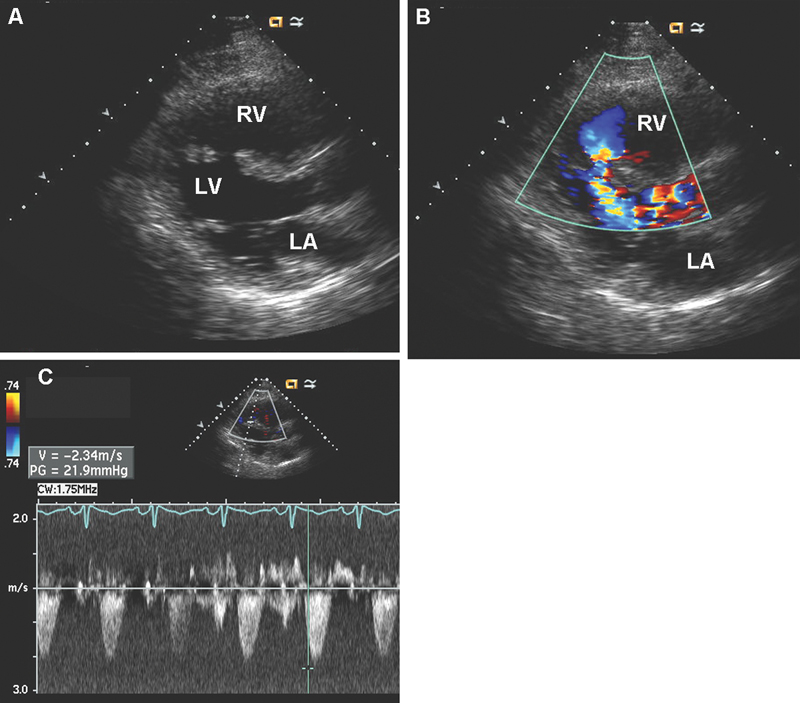

فحوصات تشخيصية لبعض امراض القلب والشرايين التاجية